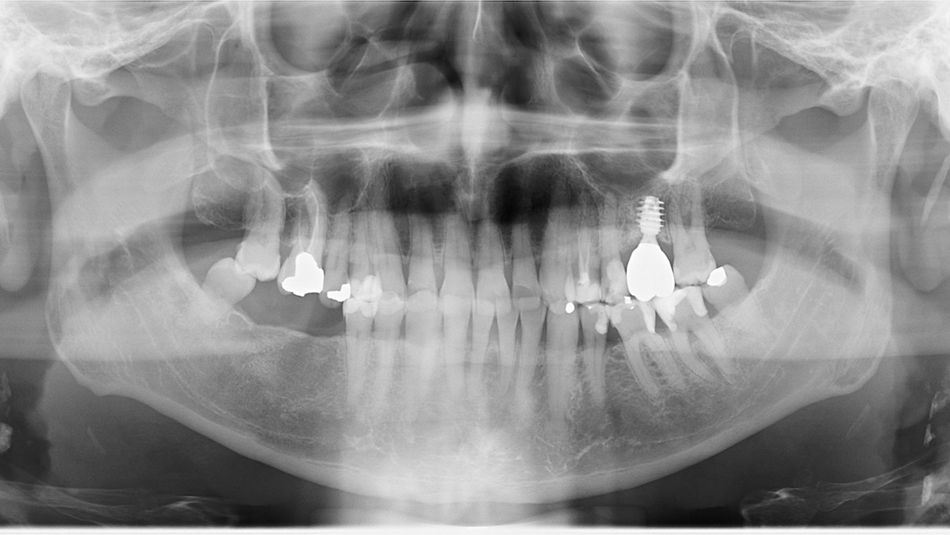

Initial situation

The patient was diagnosed by 3D CT scan and radiograph during a routine control of a classic first molar.  The clinical signs necessitated tooth extraction followed by immediate implantation, socket gap filling and placement of a sealing socket abutment to support anatomical structures.

1. Radiograph of initial situation.

1